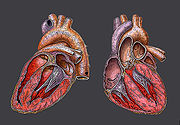

In humans, the function of the right side of the heart (see right heart) is to collect de-oxygenated blood, in the right atrium, from the body and pump it, via the right ventricle, into the lungs ( pulmonary circulation) so that carbon dioxide can be dropped off and oxygen picked up ( gas exchange). This happens through the passive process of diffusion. The left side (see left heart) collects oxygenated blood from the lungs into the left atrium. From the left atrium the blood moves to the left ventricle which pumps it out to the body. On both sides, the lower ventricles are thicker and stronger than the upper atria. The muscle wall surrounding the left ventricle is thicker than the wall surrounding the right ventricle due to the higher force needed to pump the blood through the systemic circulation.

Starting in the right atrium, the blood flows through the tricuspid valve to the right ventricle. Here it is pumped out the pulmonary semilunar valve and travels through the pulmonary artery to the lungs. From there, blood flows back through the pulmonary vein to the left atrium. It then travels through the mitral valve to the left ventricle, from where it is pumped through the aortic semilunar valve to the aorta. The aorta forks, and the blood is divided between major arteries which supply the upper and lower body. The blood travels in the arteries to the smaller arterioles, then finally to the tiny capillaries which feed each cell. The (relatively) deoxygenated blood then travels to the venules, which coalesce into veins, then to the inferior and superior venae cavae and finally back to the right atrium where the process began.